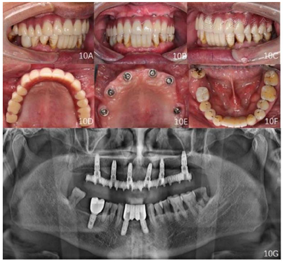

12、14、16、22、24种植一期术后12个月、26种植一期术后6个月,佩戴种植体支持式全牙列固定义齿,义齿戴入后患者唇颊侧丰满度良好,发音清晰,双侧咬合关系恢复良好。曲面体层片示种植体周围骨结合良好(图10)。

面像;E:佩戴义齿前复合基台周围软组织状况;F:下颌

面像;G:戴牙后曲面断层片

面像;G:戴牙后曲面断层片随访及转归:种植体支持式全牙列固定义齿修复后12个月复查:修复体完整稳固,表面及组织面清洁,复合基台周围软组织健康,发音清晰,正中及侧方咬合关系稳定(图11)。曲面体层片示种植体周围无透射影像。